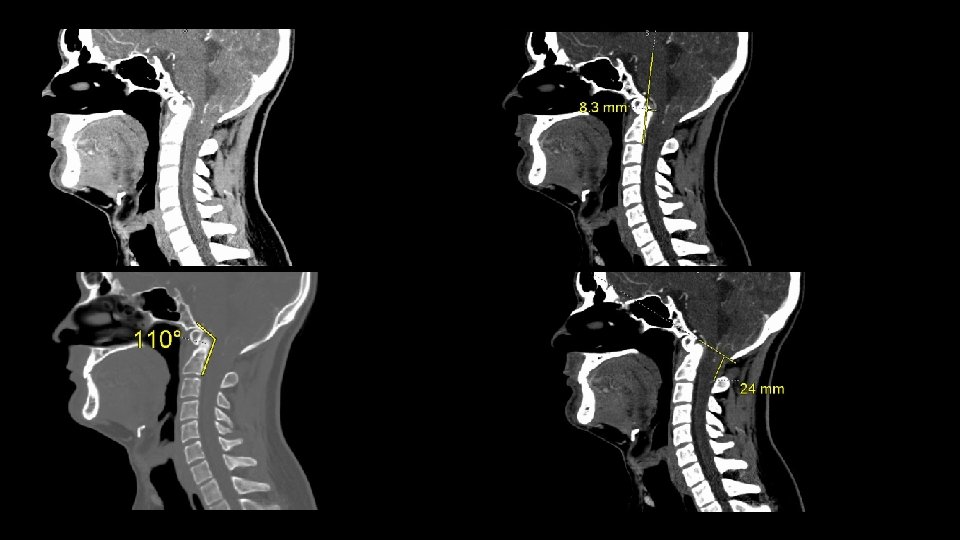

Cranio-cervical Junction (Skull base spine) • Describe anatomy in position when imaged postural • Bones • Clival axial angle • Grabb-Oakes measurement • Harris measurements • (horizontal, vertical)

Measurements at the Cranio-Cervical Junction Clival axial angle • Normal range 150 -170 degrees

Grabb-Mapstone-Oakes measurement

Grabb-Mapstone -Oakes measurement 0. 7 cm or less normal Greater than 0. 9 cm suggests utility of anterior correction prior to posterior decompression (and stabilization) Recognized following Chiari decompression without correction of anterior impingement (stabilization)

Harris horizontal measurement • • Basion-axis interval Relationship of skull base - C 1 Anterior-posterior (Front to back) Brainstem / spinal cord stress

Harris measurement measures distraction and (pathological) translation

• Harris measurement 1. 2 cm or greater implies ligamentous failure More than 0. 1 cm difference flexion -> extension abnormal • Rojas : normal is 0. 85 cm or less